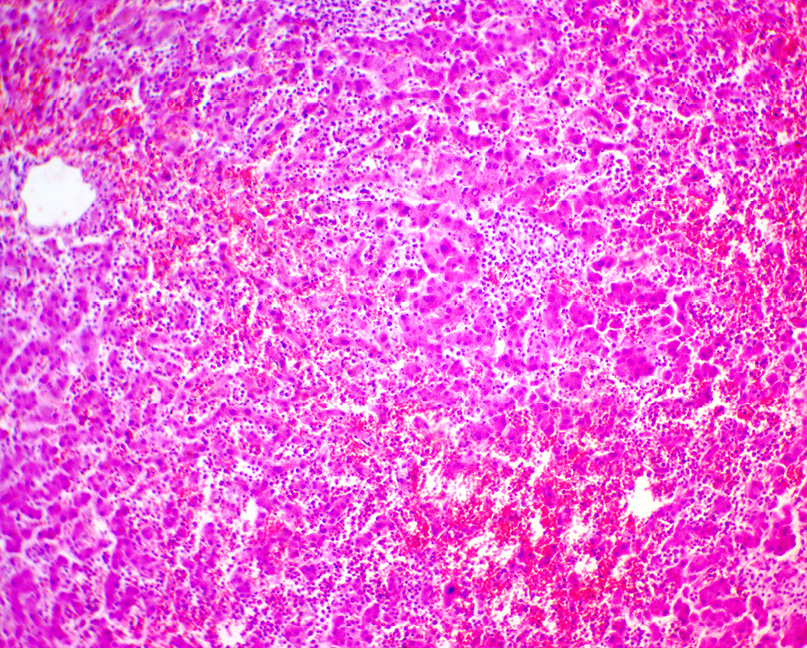

Histological examination of the heart revealed a large number of leukemic cells, most being of myelocyte morphology, and individual cells resembling monocytes and monoblasts in the lumen of the vessels and in the interstitial spaces. Similar infiltrates were found in the lungs, liver, kidneys, spleen, retroperitoneal tissue, and pancreas (Figures 1–3). In the lumen of the cerebral vessels, leukemic cells were detected in large quantities (Figure 4). The rounded kidney mass was histologically verified as clear cell renal cell carcinoma. The mucous membrane of the colon had extensive ulcerative defects extending to the submucosa and muscular membranes. In the intestinal wall, in certain fields of vision, there was infiltration of leukemic cells.

Fig. 3. Microscopic specimen of the spleen of the patient with chronic myelomonocytic leukemia. Hyalinosis of the central vein. The pattern of lymphoid follicles not determined, the pulp is represented by leukemic cells (stained with hematoxylin and eosin, magnification ×200).